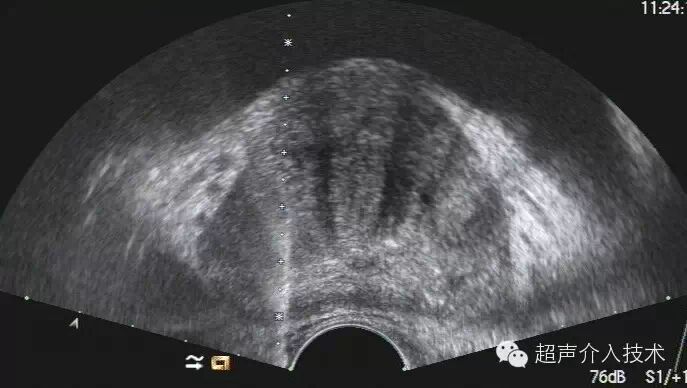

(二)超声引导下前列腺穿刺活检穿刺步骤:超声引导下前列腺穿刺活检有经直肠穿刺法和经会阴穿刺法两种。前者在端射式直肠探头引导下进行(配有专用穿刺架);后者在线阵式(或双平面)直肠探头引导下进行(不必配穿刺架)。用径向扫查直肠探头引导穿刺的方法,因定位准确度不够,现已无人采用。

1.经直肠穿刺法  在侧卧位或膝胸位,先作直肠指检,除对前列腺检查外,还需确保直肠内无粪便,否则嘱排便后再作穿刺活检。肛门周围用5%聚维酮碘溶液消毒,不需麻醉。端射式直肠探头套上灭菌树胶套(避孕套),装上灭菌的穿刺附加器(穿刺架),在探头表面涂灭菌的石蜡油或其他已灭菌的水剂润滑剂。轻轻将探头放入肛门,对前列腺、精囊由上而下作全面检查。找到目标后,调整探头方位,把待穿刺目标在超声仪屏幕上与穿刺引导线重合,再调整穿刺进针深度,打开自动活检枪保险,按动引发钮,穿刺针自动弹向靶组织,切割立即完成,即可退针。穿刺针用与自动枪相配的已消毒的一次性18G(或16G)Trucut针,针长20cm。穿刺得到的条状组织标本,放入4%甲醛溶液中送病理检验。多点穿刺所得到标本,必须编号,分别放入盛器,并注明病人姓名和穿刺部位,以免弄错。

2.经会阴穿刺活检法  患者取截石位,如在普通诊察床上进行穿刺,应垫高臀部,托起阴囊,用胶布固定。先作直肠指检,了解前列腺及直肠情况。会阴部皮肤用5%聚维酮碘溶液常规消毒,用线阵(或双平面)直肠探头(5.0~7.5MHz)按常规放入肛门,显示前列腺,转动探头,找到待穿刺目标,测量待穿刺靶组织距探头表面距离。然后用18G或16GTrucut针(配自动枪),在2%利多卡因局麻下作会阴穿刺。穿刺针必须与棒杆状探头保持平行,进针部位根据上述测得的距离和探头旋转的角度决定,务必使穿刺针与待穿刺目标能同时在屏幕上清晰显示。经会阴穿刺不必用穿刺架。经会阴穿刺能看到穿刺针进入前列腺的全过程。手动法在穿刺针接近目标处按常规穿刺步骤进行;自动活检枪在接近病灶处打开保险钮,按动引发钮,穿刺针的针芯和针鞘先后自动弹射向靶组织,切割立即完成,即可退针。穿刺得到的条状组织处理办法同经直肠穿刺法。拔针后,穿刺部敷以纱布,即可自行回家。